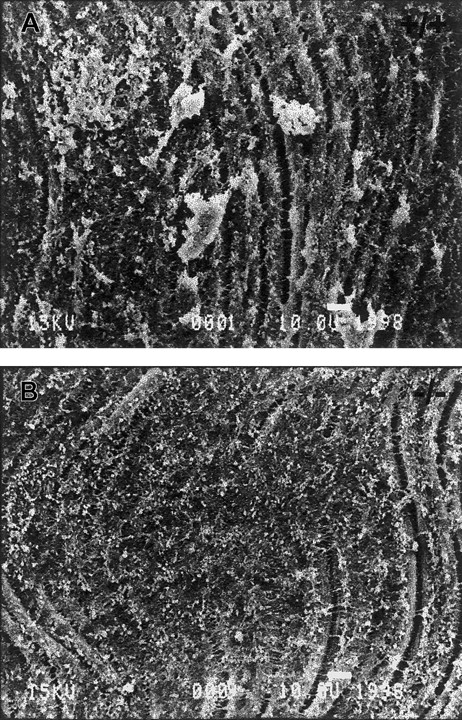

To examine the ability of TSP2-null platelets to form aggregates following vascular injury, the endothelium of the left common carotid artery of anesthetized mice was denuded by the insertion and rotation of a flexible nylon loop. Circulating platelets were allowed to interact with the exposed subendothelium for 10 minutes, and the arteries were then perfused-fixed in situ, harvested, processed, and analyzed by SEM and TEM. SEM analysis revealed the formation of numerous platelet aggregates on the exposed subendothelium of wild-type animals (Figure 1A). These aggregates ranged in size from 10 to 75 μm in diameter. On the contrary, large platelet aggregates, over 10 μm in diameter, were absent from the exposed subendothelium of TSP2-null mice (Figure 1B), although we observed many single platelets as well as small platelet aggregates. This observation suggests that the adhesion of platelets to the exposed subendothelium was not primarily compromised. In experiments in which the carotid arteries were harvested 15 minutes following denudation, we observed that larger platelet aggregates were beginning to form in TSP2-null mice, but these aggregates were still significantly smaller than those in wild-type mice (data not shown). Thus, we conclude that conditions in TSP2-null mice led to a delay in platelet aggregation.

TSP2-null mice fail to form platelet aggregates normally in vivo.

Representative SEM images of denuded carotid artery subendothelium 10 minutes following injury. Numerous platelet aggregates can be seen in wild-type mice (A), whereas none are observed in TSP2-null mice (B). A total of 5 mice per genotype were analyzed. Bar represents 10 μm.